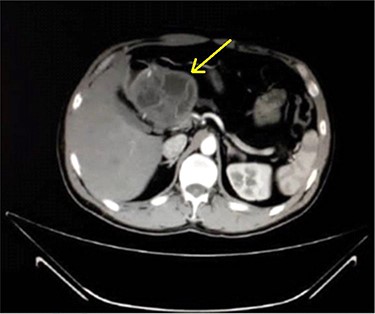

A 33-year-old male was referred to our Department of General Surgery, with a 3-month severe epigastric pain radiating to the back, associated with several episodes of green vomiting. Pain is episodic, relieved by painkillers, has no relation to food or movement. No history of changes in bowel habits or urine color. The patient reported a history of early satiety and an observed unmeasured weight loss. The past medical and surgical histories were irrelevant. Abdominal examination showed tenderness in the epigastric region, with no other signs. Laboratory tests including complete blood cell count, renal and liver function tests were within normal levels. Immunologic methods (ELISA) and indirect hemagglutination (IHA) assays were negative. Serum Amylase and CA 19-9 were within normal levels. Computed tomography (CT) scan revealed a multilocular cystic lesion in the head of the pancreas measuring 9.5 × 8.2 × 11 cm, causing external compression on the distal part of the CBD. The main pancreatic duct near the cystic mass is dilated measuring 0.5 cm. The gallbladder is distended (Figs 1 and 2).

Axial contrast-enhanced CT scan of the abdomen demonstrating a well-defined solitary cystic lesion in the head of the pancreas with a diameter of (9 cm).

Axial contrast-enhanced CT scan of the abdomen showing dilatation of the MPD (5 mm).